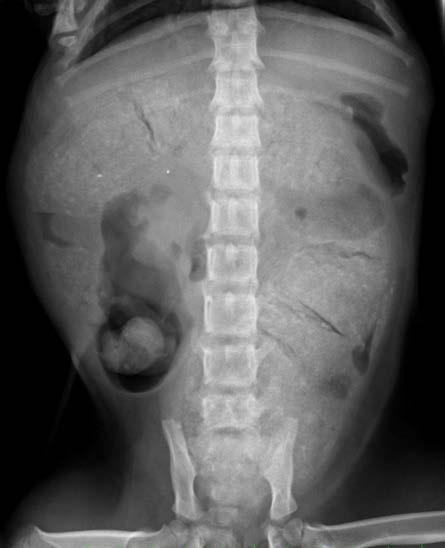

Diagnóstico por imagen Los hallazgos no son específicos de pacientes infecta dos con parvovirus. Las radiografías abdominales pue den ser normales al inicio de la enfermedad, o mostrar signos de íleo con distensión de asas intestinales por acúmulo de líquido o gas. Los signos ecográficos son asimismo inespecíficos, mostrando áreas de distensión con fluido y gas tanto en estómago como en intestino, íleo con movimientos peristálticos inefectivos, efusión peritoneal anecoica, etc.1,2,5,6 Ambas técnicas ayudan a descartar otras causas del cuadro clínico, como son cuer pos extraños, obstrucción e invaginación intestinal.1,2,5,6